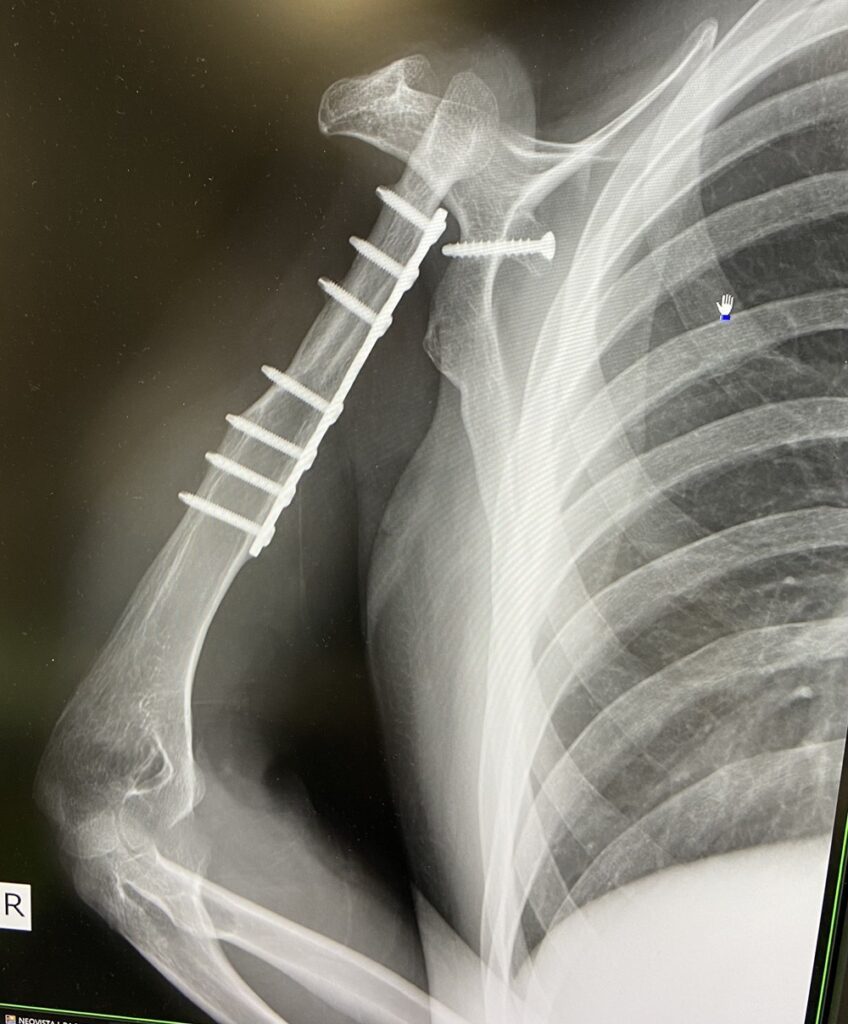

レントゲン写真(@miyabi_udenashiさんより提供)